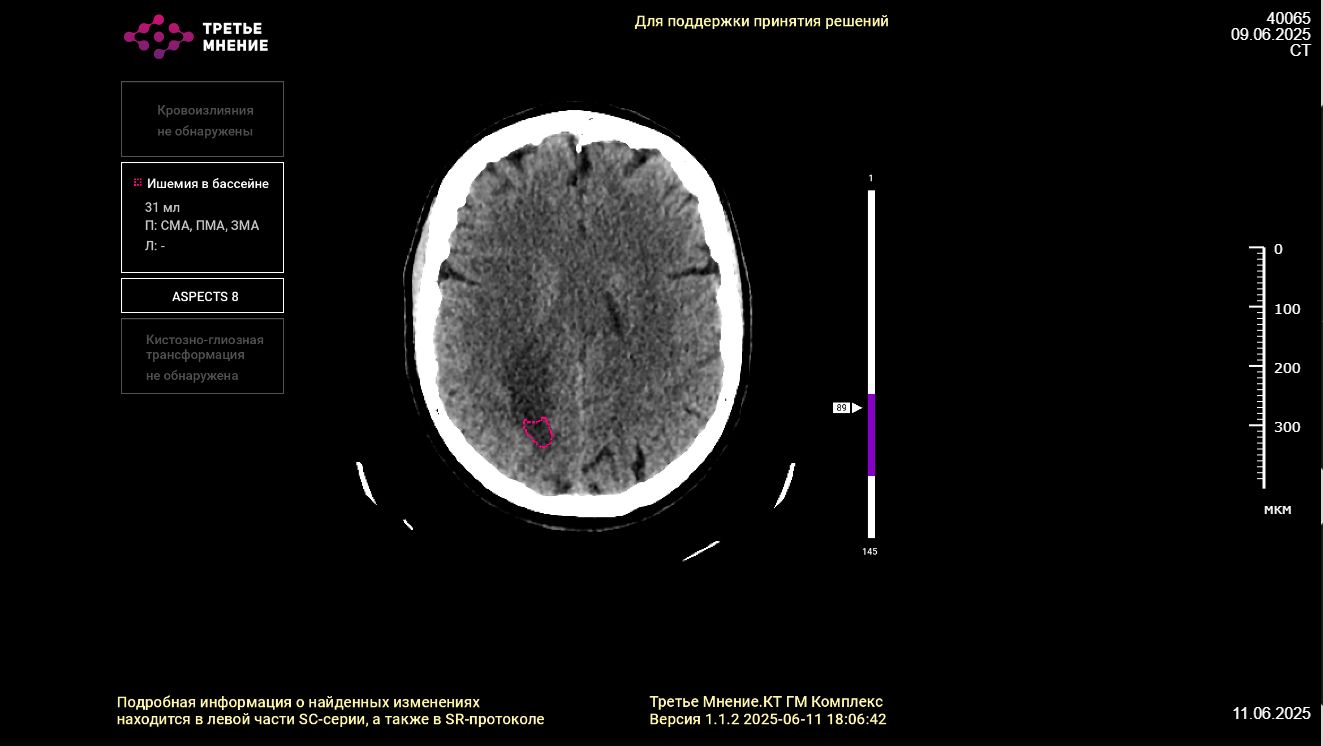

«Искусственный интеллект ищет заданные врачом патологии и проверяет снимок на другие потенциальные заболевания. Так, например, анализируя КТ-снимок пациента с переломом ребер, ИИ параллельно ищет признаки онкологии и пневмонии. Свои находки программа транслирует врачу в формате не только текста, но и рисунка – выделяет очаги фиолетовыми кружками на снимках. Далее специалист либо соглашается с ИИ, либо нет. В среднем процент согласия на текущий момент составляет около 80 процентов», – объяснила директор Медицинского информационно-аналитического центра областного Минздрава Татьяна Антохова.